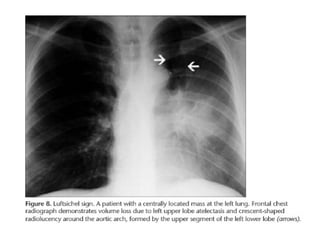

• Luftsichel sign

• The word “Luftsichel” in German means “air

crescent”. This sign is seen in severe left upper

lobe collapse. Due to the lack of a minor fissure

on the left side, upper lobe collapse causes

vertical positioning and anterior and medial

displacement of the major fissure. The superior

segment of the left lower lobe migrates superior

and anteriorly between the arch of the aorta and

the atelectatic lobe. The crescent-shaped

radiolucency around the aortic arch is called the

Luftsichel sign

• Left upper lobe collapse.

This radiograph shows an

opacity that is contiguous

with the aortic knob, a

smaller left hemithorax,

and a mediastinal shift.

The luftsichel sign

involves hyperextension

of the superior segment

of the left lower lobe,

which then occupies the

left apex

• Luftsichel sign •The word “Luftsichel” in German means “air crescent”. This sign is seen in severe left upper lobe collapse. Due to the lack of a minor fissure on the left side, upper lobe collapse causes vertical positioning and anterior and medial displacement of the major fissure. The superior segment of the left lower lobe migrates superior and anteriorly between the arch of the aorta and the atelectatic lobe. The crescent-shaped radiolucency around the aortic arch is called the Luftsichel sign

• Left upperlobe collapse. This radiograph shows an opacity that is contiguous with the aortic knob, a smaller left hemithorax, and a mediastinal shift. The luftsichel sign involves hyperextension of the superior segment of the left lower lobe, which then occupies the left apex